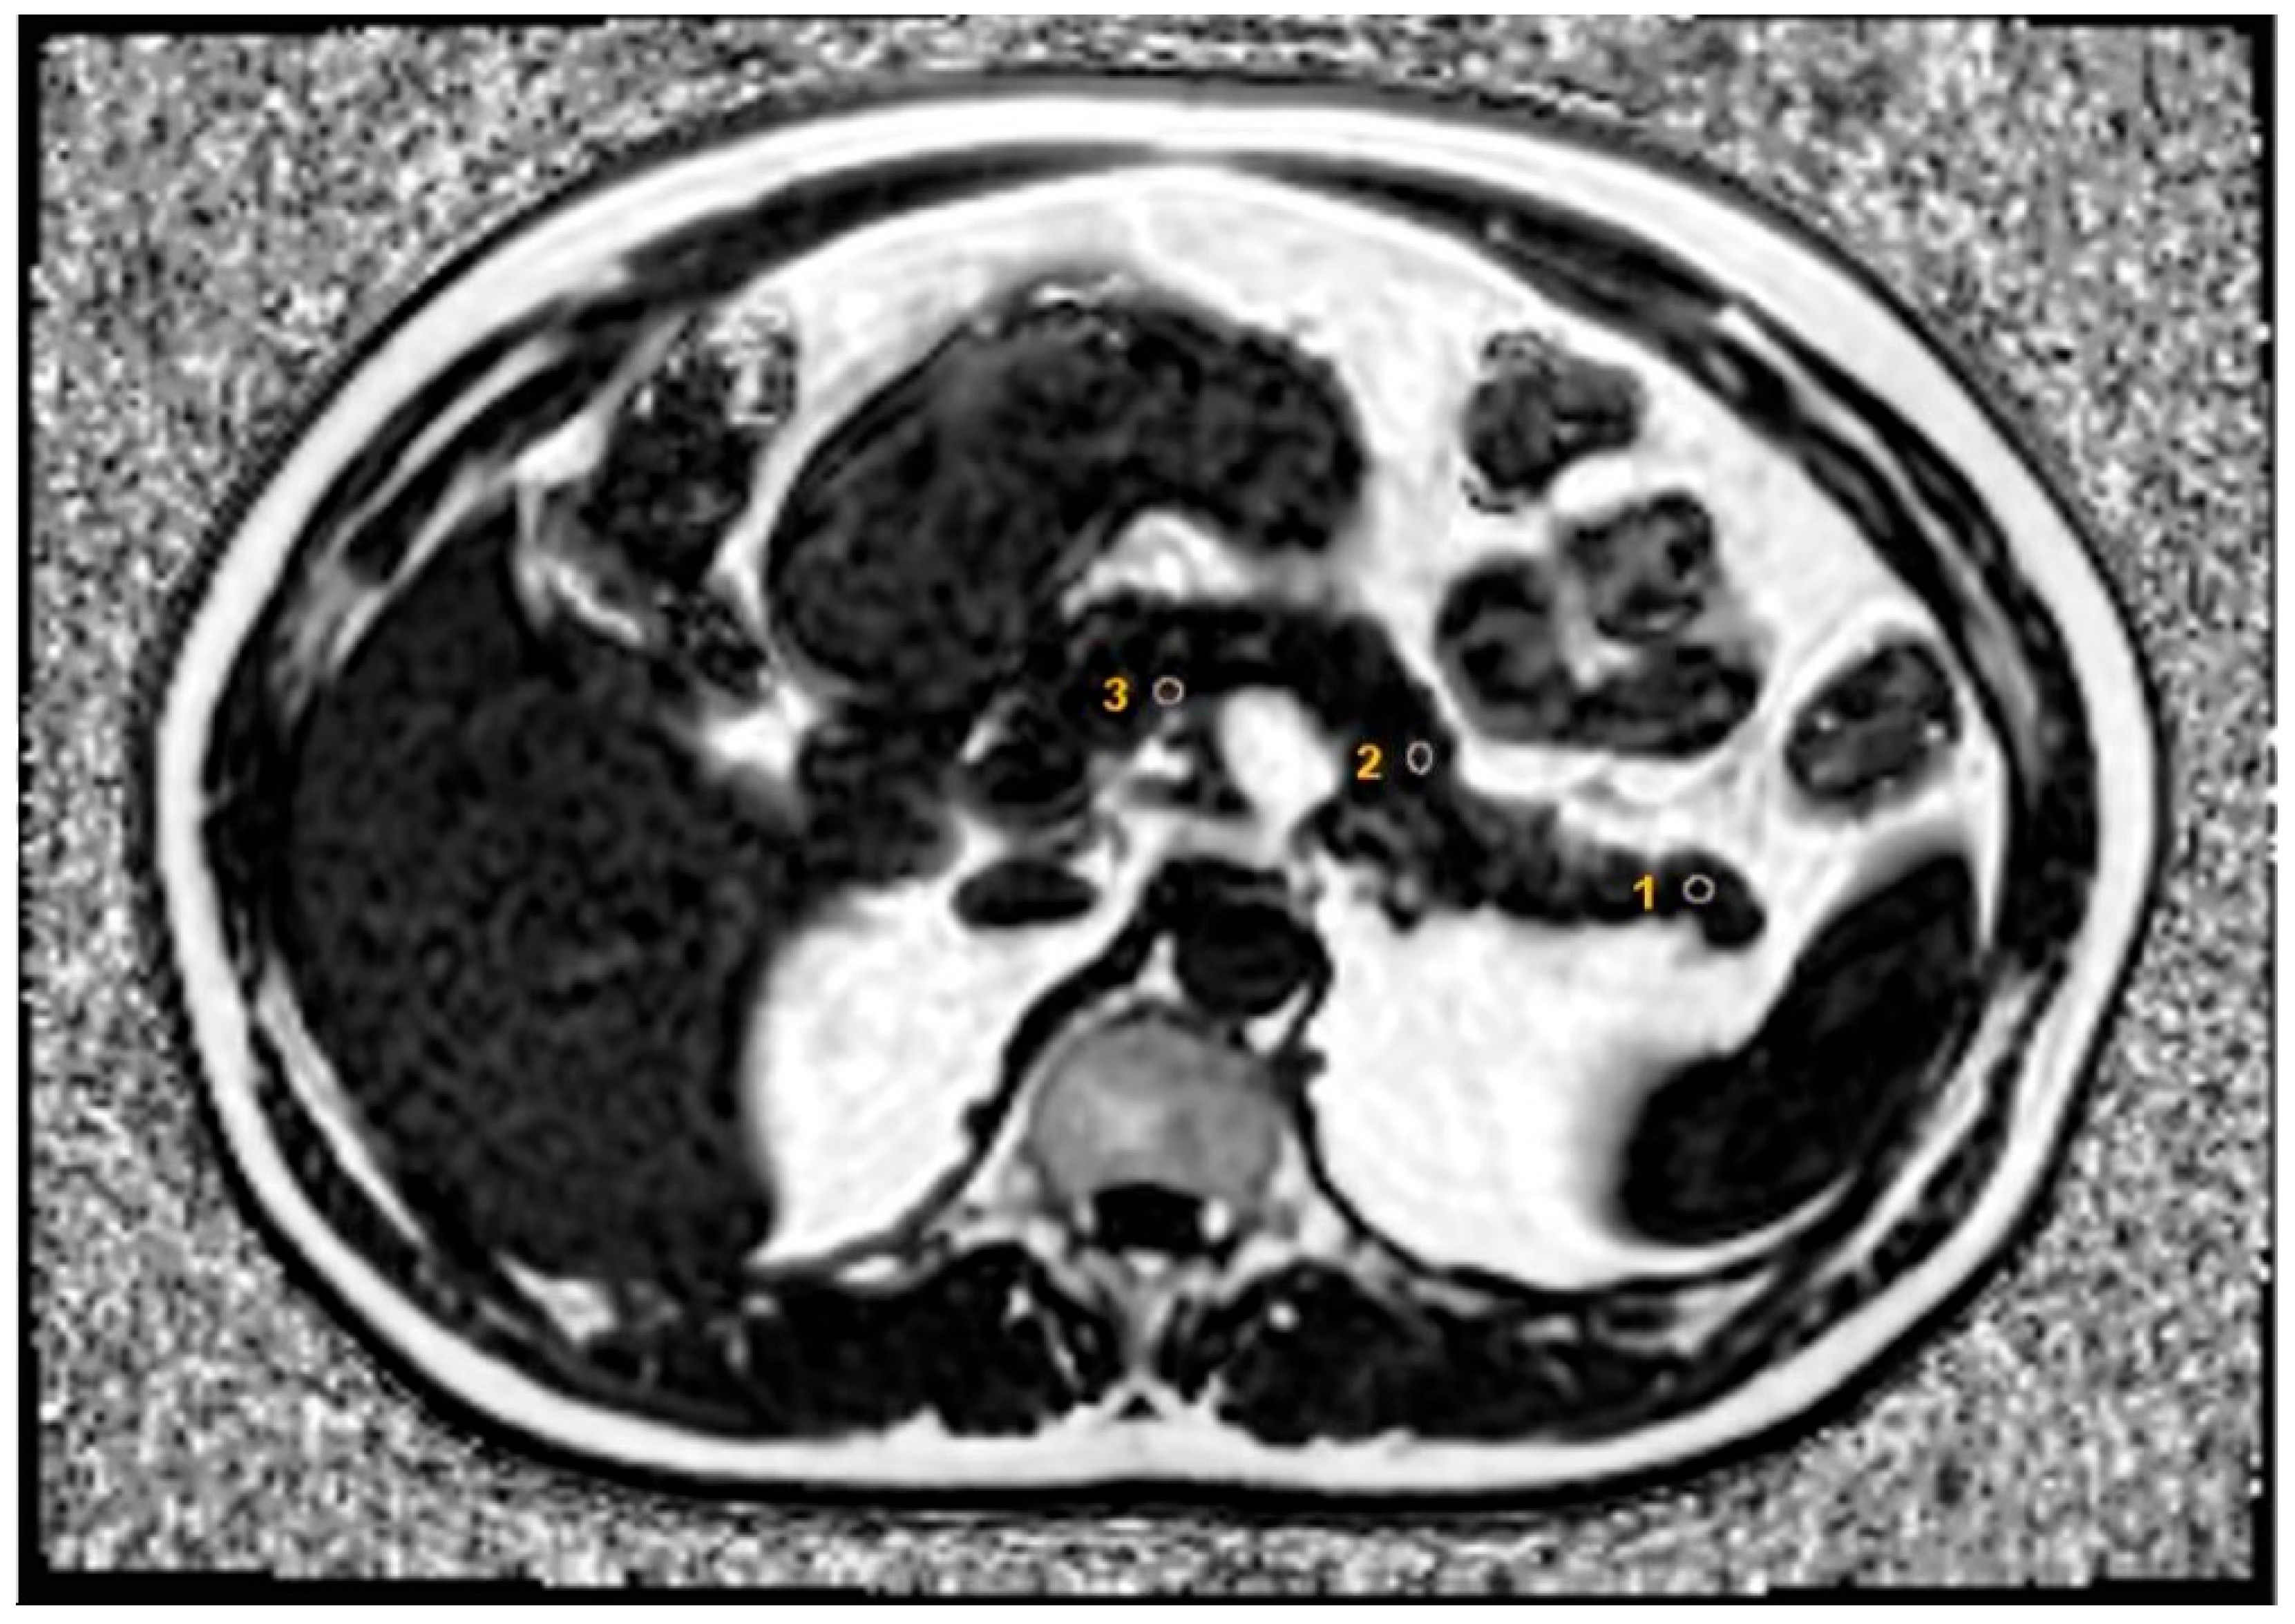

2.3. MRI Measurements